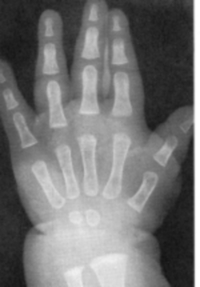

Sexo Masculino

3 meses

idade óssea - 3m